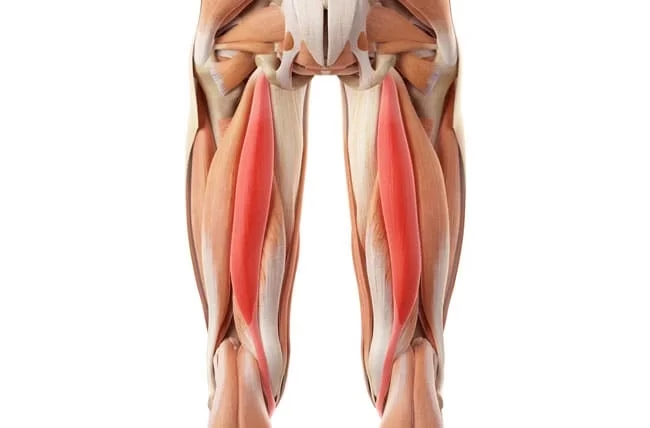

Anatomía y Función de los Isquiotibiales: Clave para el Movimiento

¿Qué son los isquiotibiales y por qué son tan importantes?

Los isquiotibiales son un grupo muscular potente y fundamental, situado en la parte posterior del muslo. Están compuestos por tres músculos principales: el bíceps femoral (con sus dos cabezas), el semitendinoso y el semimembranoso. Estos músculos se originan en la tuberosidad isquiática (parte inferior de la pelvis) y se insertan en la tibia y el peroné, justo debajo de la rodilla.

Su función principal es crucial para el movimiento humano y deportivo: son los principales encargados de la extensión de la cadera (llevar la pierna hacia atrás) y la flexión de la rodilla (doblar la pierna). Esto los convierte en protagonistas de actividades cotidianas como caminar, pero especialmente en movimientos explosivos y de alta demanda como correr, saltar, esprintar o patear. La correcta función de estos músculos es vital no solo para el rendimiento, sino también para la estabilidad de la rodilla y la prevención de lesiones en otras zonas. De hecho, cuando los isquiotibiales están débiles, acortados o desequilibrados, se incrementa el riesgo de sufrir lesiones no solo en el muslo, sino también en áreas adyacentes debido a compensaciones musculares y desequilibrios que pueden llevar a la amnesia glútea o problemas lumbares. Por lo tanto, la fuerza y flexibilidad de los isquiotibiales son indispensables para cualquier deportista.